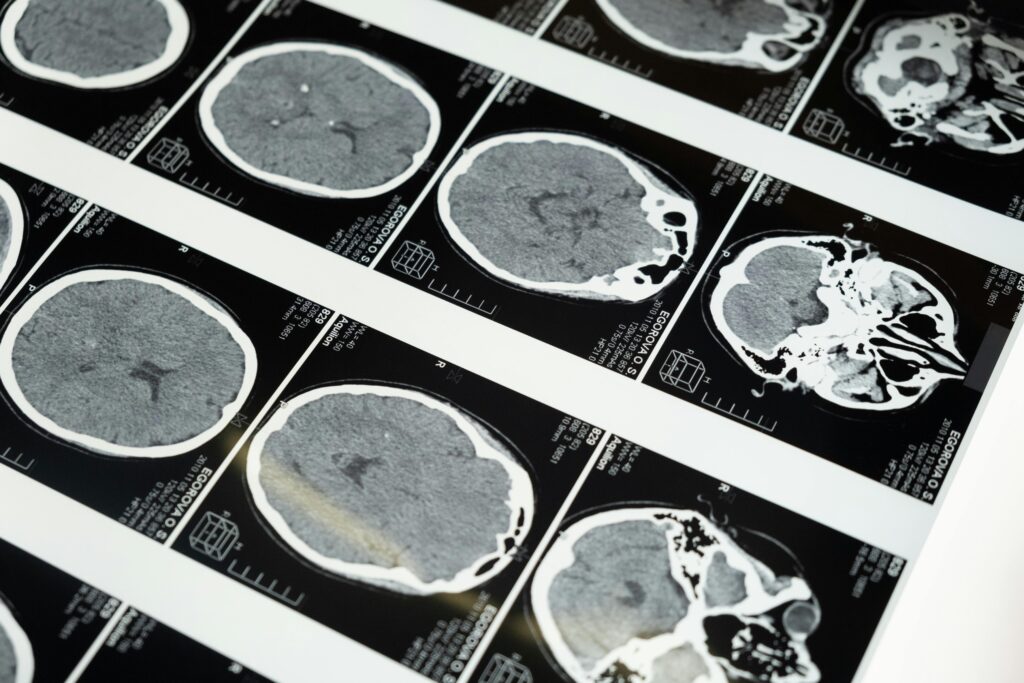

Essas doenças afetam o cérebro. A mais conhecida nos humanos é a doença de Creutzfeldt-Jakob (DCJ). Ela causa perda de memória, alterações de comportamento e de movimentos. A progressão é acelerada e leva ao óbito.

Doenças priônicas afetam o cérebro. São raras, mas perigosas.

O que acontece no cérebro

Vamos simplificar o mecanismo. Todos nós temos a proteína priônica normal (PrPC). Em condições que ainda estamos desvendando, parte dela muda de forma e vira PrPSc, a forma “errada”. Essa forma atua como molde. Encosta na proteína normal e a faz copiar o mesmo erro. É um efeito dominó molecular.

Com o tempo, esses “blocos” mal dobrados se juntam e formam agregados. Eles são rígidos, parecidos com fibras. No tecido, vemos lesões microscópicas que lembram uma esponja. O resultado é perda de neurônios e de funções cerebrais.